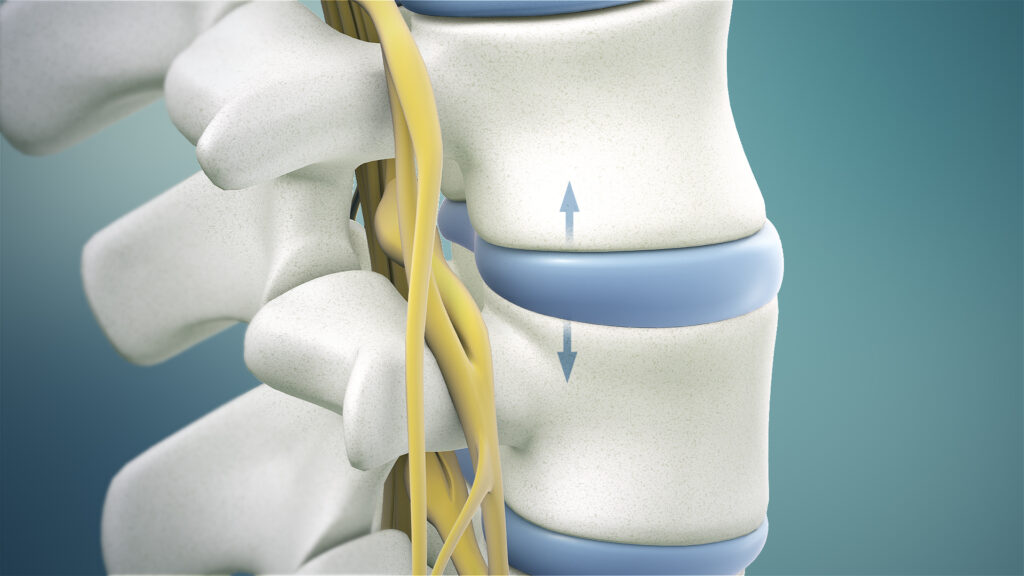

Osteoarthritis of the spine, sometimes called spinal osteoarthritis, is a degenerative joint condition where the protective cartilage in the spinal joints gradually breaks down. It most commonly affects the neck (cervical spine) and lower back (lumbar spine).

As the cartilage wears away, the bones can rub against each other, leading to pain, stiffness, reduced mobility, and sometimes inflammation. In some cases, bone spurs (osteophytes) may also develop, which can further contribute to discomfort or nerve irritation.

- Spinal decompression – Removal of bone or tissue pressing on nerves to reduce pain and neurological symptoms.

- Spinal fusion – Joining two or more vertebrae to stabilise the spine in cases of severe degeneration.